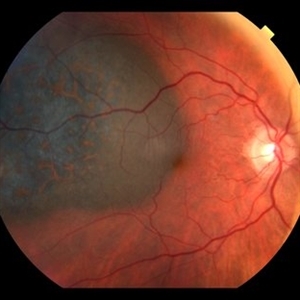

Orange Pigment Overlying a Lesion Suspicious for a Choroidal Melanoma

Orange Pigment Overlying a Lesion Suspicious for a Choroidal Melanoma

Jan 16 2019 by John S. King, MD

76-year-old white male saw his eye doctor with a three week complaint of photopsias and a shadow in his vision. Found to have a 10.5/12.5/2.5 (medium reflectivity) pigmented, choroidal mass associated with SRF and orange pigment (hyper-autofluorescence of lipofuscin), and without drusen or halo. See photo

Photographer: Stacey Coleman

Imaging device: Topcon 50

Condition/keywords: lipofuscin, orange pigment